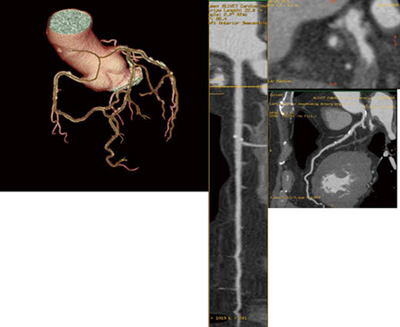

心臓解析アプリケーションにおいては,オートメーション機能を進化させた。冠動脈解析時,RCA,LAD,LCX,そして各分枝までをプロトコールの選択のみで自動的にトラッキングされ(AutoTracking機能),画像処理は完了する。冠動脈の直交断面における中心軸追従性の飛躍的な向上が実現した結果,自動トラッキングが可能になったとも言える(図1)。

図1 自動トラッキング画面